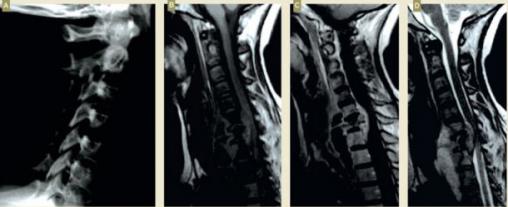

A. Radiographie standard ; B. T1 ; C. T1 + gadolinium ; D. T2.Les spondylodiscites tuberculeuses représentent environ 2 % des cas de tuberculose. Une spondylodiscite tuberculeuse peut se manifester par une douleur isolée. Le diagnostic repose sur l’IRM.